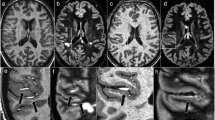

EPSI allowed detection of neuro-metabolites in the visual tract WM of MS patients [5]. In this study, EPSI was used to study neurochemical changes at 1.5 T associated with visually evoked potential (VEP) abnormalities. It was found that the average value of NAA is significantly lower (p ≤ 0.05) in the abnormal VEP group than in the normal VEP group. 3D-MRSI was implemented using EPSI techniques at 1.5 T [114] to measure the major metabolite ratios in control and MS cohorts from two ROIs: supratentorial brain and central brain. This study was performed at long TE (144 ms) on three subtypes of MS: RRMS, PPMS and SPMS, where it was found that NAA/Cr ratio was significantly decreased (p < 0.01) for all MS cohorts compared to HCs in both ROI. Sample spectroscopic data from SPMS patients are shown in Fig. 12.

Spectroscopic data from a typical SPMS brain from three separate regions: [1] MS lesion, [2] CGM and [3] NAWM. The voxels are represented by the numbers and red spots. Experimental parameters: 3D-EPSI (TE/TR = 144/2000 ms), acquisition time (20 min), FOV (24 × 24 × 8 cm3) and slice thickness (4 mm) at 1.5 T. Reproduced with permission from [114]